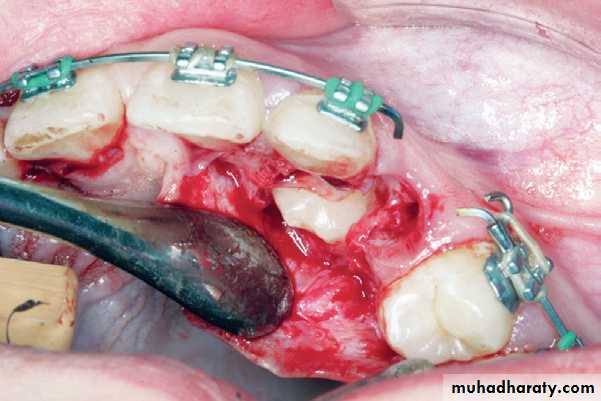

Extraction Using Labial Approach

Radiograph showing impacted maxillary canines. Right canine is located labially while left canine is located palatally

Clinical photograph of the labial area where the right canine is localized labially

right canineSurgical procedure for removal of right impacted canine. A trapezoidal incision is created buccally. It is desirable to make an intersulcular incision extending to at least one to two teeth in each direction from the area of interest

Reflection of the mucoperiosteal flap

Note: A common error is to develop a small flap and extend it conservatively. This approach, although reasonable in theory, in practice often leads to tearing of the flap and/or inadequate exposure, ultimately resulting in a poor outcome. A well planned and properly retracted large flap generally heals as well, if not better, than a traumatized small flap.A round bur is used to remove the bone covering the crown of the tooth

Complete exposure of the crown of the tooth and part of the root